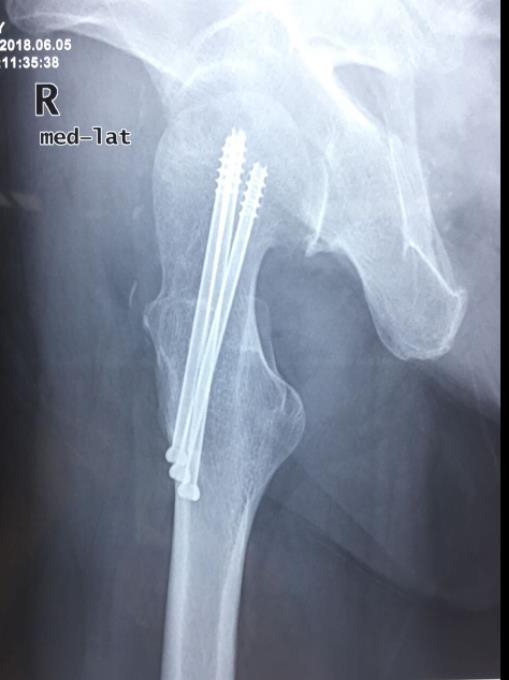

2、标准放置螺钉为倒三角形,其中下方螺钉在股骨矩,后方螺钉在后方骨皮质、研究发现倒三角形平行三枚螺钉能提供最佳的固定强度;

3、螺钉位于股骨颈四周,特别是后侧及下方,避免低于小转子方向进针,可能导致术后转子下骨折;

4、两个平面透视导针位置良好后切开皮肤,空心钻铭孔,导针引导下拧入空心钉,空心钉确保所有螺纹位于骨折线近端,螺钉头应距离软骨下骨5mm。

根据复查骨折愈合情况,骨折固定术后12周内可进行脚尖点地负重锻炼,12周后开始部分负重锻炼。

空心钉固定的三原则:“贴边、平行、倒品”

1、贴边是指3枚螺钉在股骨颈内,尽量靠近外围皮质。这样3枚螺钉作为一个整体,对整个骨折面可形成面状加压,如果3枚螺钉不够离散,更趋于点状加压,稳定性较差,不能较好地对抗扭转和剪切。

有研究显示,在侧位片上,螺钉的前后分布越分散,骨折不愈合发生率越低。J Bone Joint Surg Br. 2005 May: 87(5): 632-4.

图1 3枚螺钉在股骨颈内的理想位置

2、倒品有更明显的生物力学优势,CORR曾发表美国学者的一项生物力学研究,对比两种固定方式出现再骨折的负荷大小,发现倒三角再骨折的平均负荷11330N,而正三角仅7795N,差异明显,也就是说倒三角形固定可使再骨折的负荷提升45%。

图2 倒品字固定

3、平行生物力学更稳定。